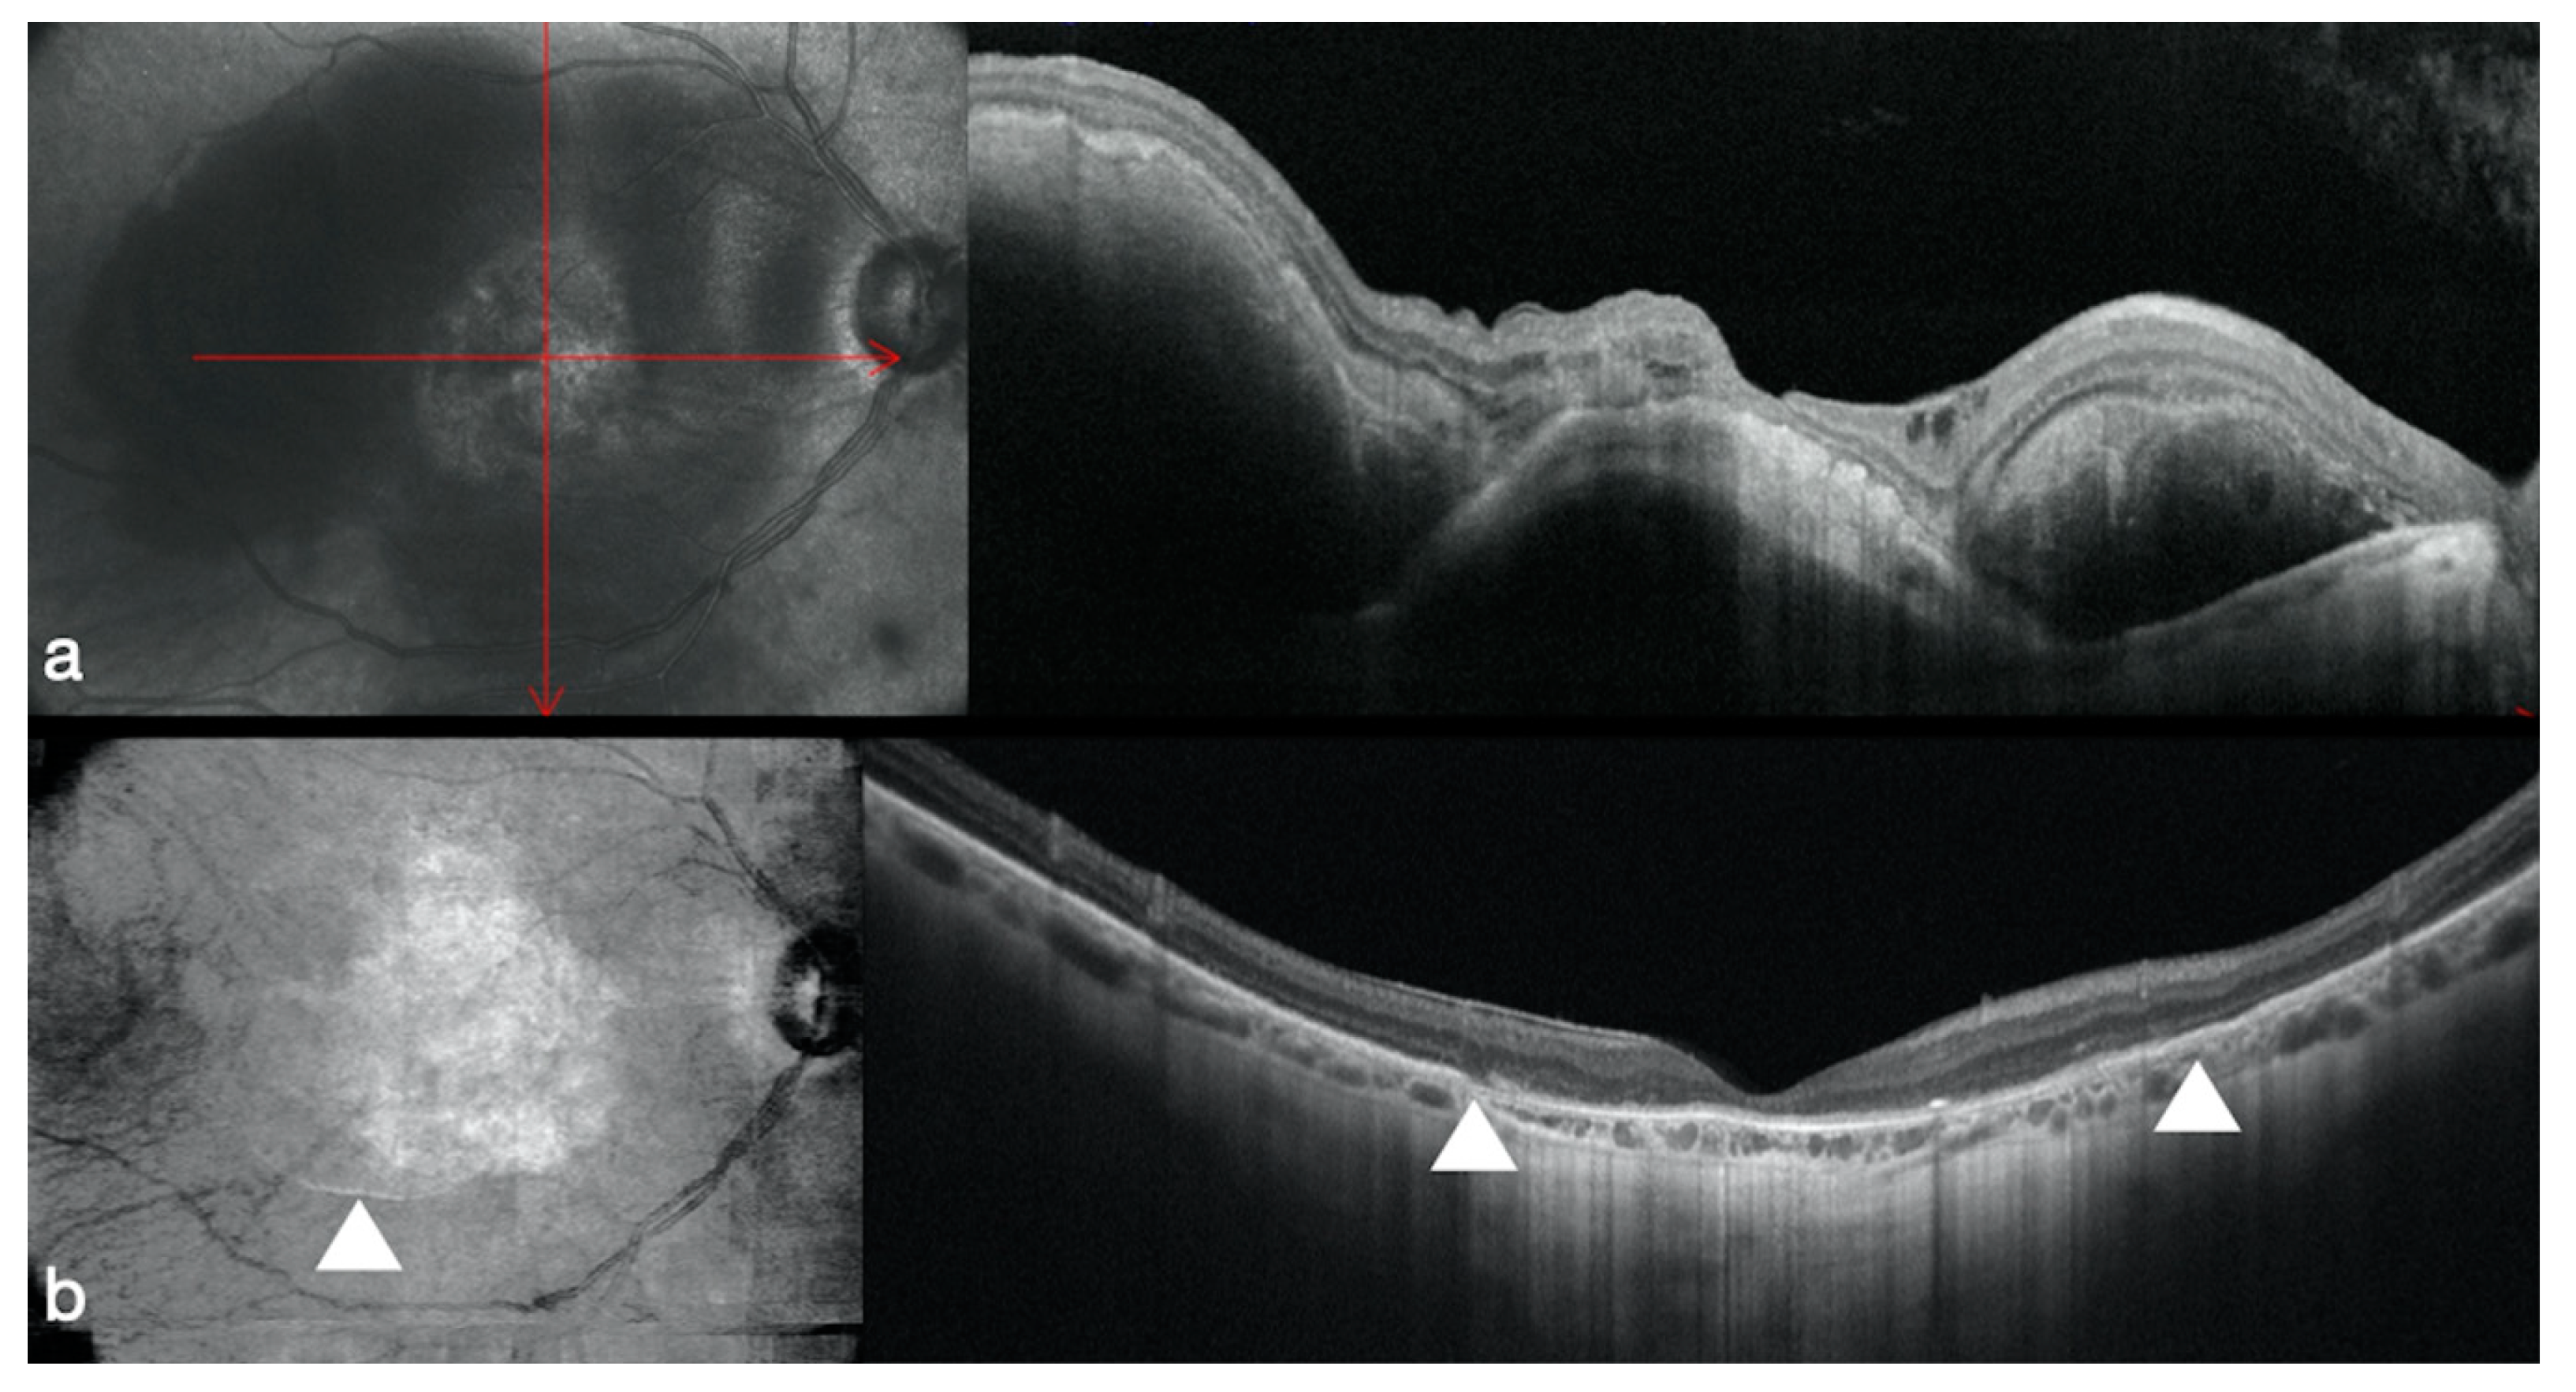

3.4. Optic Disk Pit Associated Macular Detachment

- Rizzo, S.; Caporossi, T.; Pacini, B.; De Angelis, L.; De Vitto, M.L.; Gainsanti, F. Management of Optic Disk Pit-associated Macular Detachment with Human Amniotic Membrane Patch. Retina 2020. [Google Scholar] [CrossRef] [PubMed]

3.5. Age-Related Macular Degeneration

- Rizzo, S.; Caporossi, T.; Tartaro, R.; Finocchio, L.; Pacini, B.; Bacherini, D.; Virgili, G. Human Amniotic Membrane plug to restore Age related Macular Degeneration photoreceptors’ damage. Ophthalmol. Retin. 2020. [Google Scholar] [CrossRef]